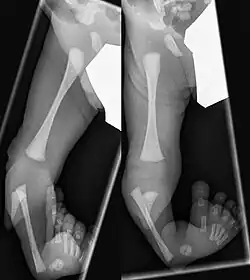

Kongenitale Tibiale Hemimelie Typ I

Kongenitale Tibiale Hemimelie Type II

Congenital Tibiale Hemimelie Typ III

Für die Behandlung gebräuchlich ist die Klassifikation nach Kalamchi und Dawe:[6]

• Typ I Aplasie der Tibia, Fuß adduziert, + eventuell fehlende Strahlen medial

• Typ II Tibia nur distal fehlend, Artikulation zum Femur erhalten

• Typ III Dysplasie der Tibia distal mit tibiofibulärer Diastase (Fehlanlage der Sprunggelenksgabel)

Bereits im Mutterleib kann während einer Ultraschalluntersuchung die Fehlbildung erkannt werden,[2] die Verkürzung und Fehlstellung des Unterschenkels ist nach der Geburt offensichtlich. Ein Röntgenbild kann das Ausmaß der Fehlbildung sowie zusätzliche knöcherne Veränderungen dokumentieren. Mittels Sonographie können die knorpeligen Anlagen und deren Stellung zum Gelenk sicher dargestellt werden, wesentlich bei den Typen II und III.